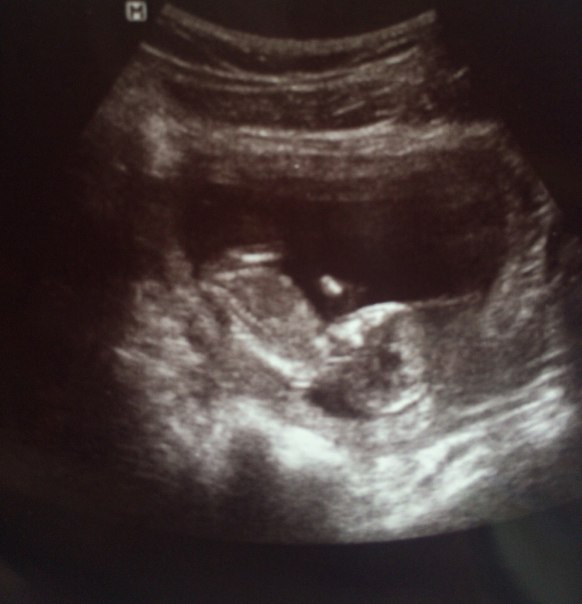

жду мальчика, 23 неделя

Фото мое, со скрининга!Мы Вам с сыночком желаем исполнения самого заветного желания) А я с сыном договорюсь, чтобы он поторопил Ваших ангелочков